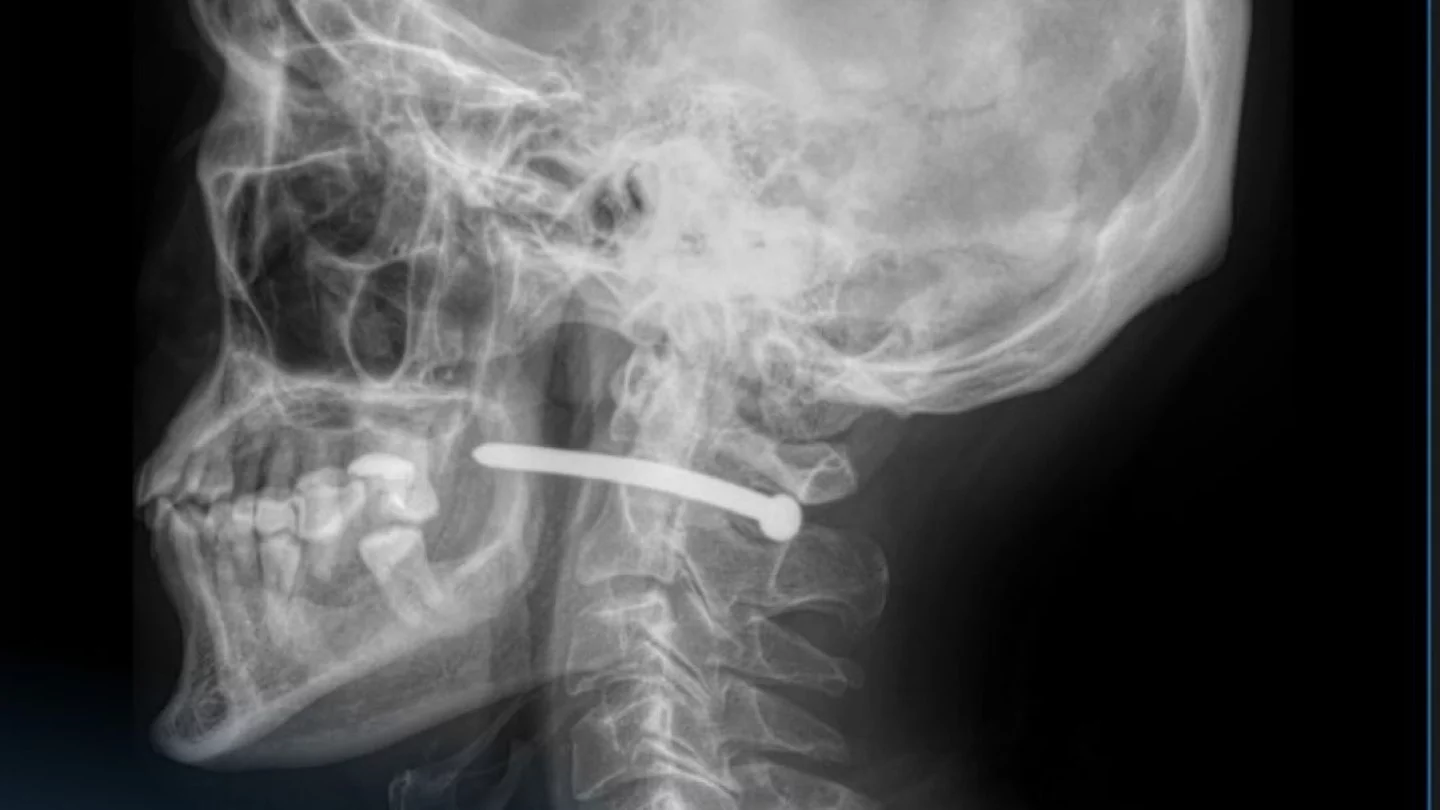

Мужчина случайно выстрелил себе в шею гвоздём в Петропавловске

Изображение: Многопрофильная городская больница Петропавловска

51-летний пострадавший получил травму во время ремонта, работая с пневматическим пистолетом. Мужчине чудом повезло — жизненно важные структуры оказались не задеты, сообщает Orda.kz.

Житель Петропавловска обратился в многопрофильную городскую больницу скорой медицинской помощи с раной за ухом. После рентген-исследования выяснилось, что гвоздь прошёл рядом с шейным отделом позвоночника.

Хирурги вытащили гвоздь, обработали рану и наложили швы. После этого пациента отпустили домой.

Как отмечают медики, травмы в области шеи крайне опасны — рядом проходят крупные сосуды, нервы, дыхательные пути и спинной мозг. Даже небольшое повреждение может привести к серьёзным последствиям. Так что мужчине действительно крупно повезло.